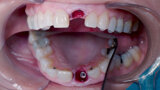

Fig. 5: Initial osteotomy with needle drill.